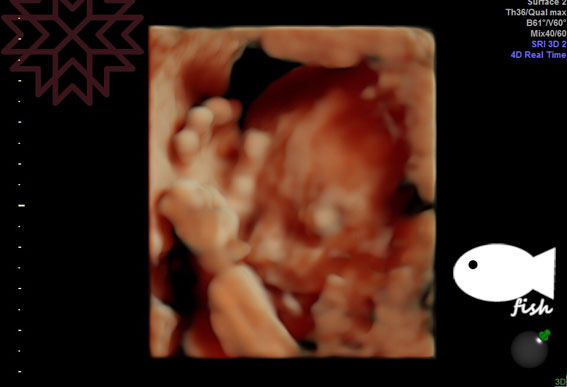

最後附上寶寶手遮臉的相片

(媽媽內心話:這種相片超可怕的啊)